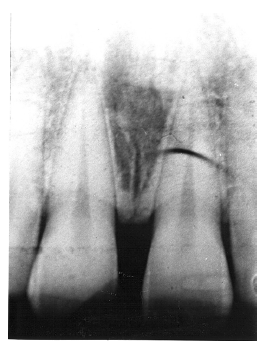

The periapical granuloma represents the body’s defense mechanism attempting to wall off irritants draining from a non-vital dental pulp. While they cannot be radiologically differentiated from abscesses or cysts, they can be differentiated from normal anatomical landmarks such as the incisive fossa because the periodontal ligament space is widened and the lamina dura is not continuously intact.

Figure 13 illustrates apical periodontal pathosis in the area of the right central incisor. Note the loss of continuity of the lamina dura and the widened periodontal ligament space on the affected side.

Figure 13 - Apical Periodontal Pathosis

Figure 13